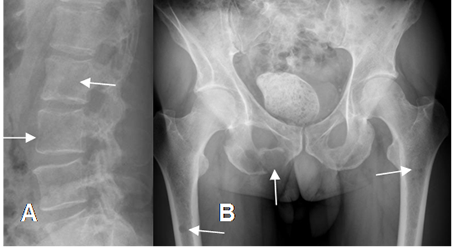

Fig 192. Mieloma.

A: Rx lateral y B: Rx AP. Lesiones líticas y de bordes definidos, pero no escleróticos, en las vértebras, fémur y ramo isquiopúbico, por mieloma.